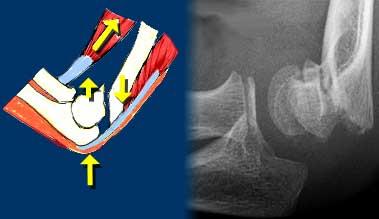

Sự căng phồng của khớp sẽ khiến đệm mỡ phía trước bị nâng lên và đệm mỡ phía sau trở nên hiện rõ.

Vùng thấu quang phía trước bị nâng cao hoặc vùng thấu quang phía sau hiện rõ trên phim X-quang thẳng nghiêm thực sự của khuỷu tay gấp 90° được mô tả là dấu hiệu đệm mỡ dương tính (hình).

Tràn máu khớp gây ra sự dịch chuyển lên trên của đệm mỡ trước và sự dịch chuyển ra sau của đệm mỡ sau.

Tình trạng tràn máu khớp sẽ dẫn đến sự dịch chuyển của đệm mỡ phía trước lên trên và đệm mỡ phía sau ra phía sau.